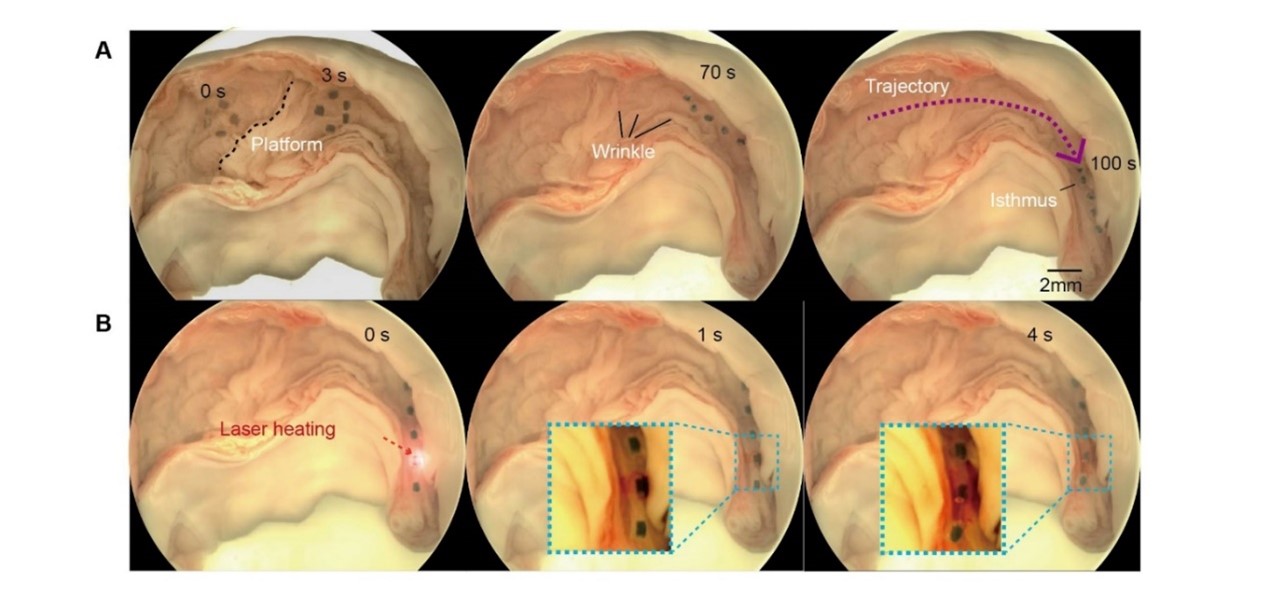

通過在離體豬輸卵管中控制微型軟體機(jī)器人執(zhí)行自適應(yīng)多模態(tài)運(yùn)動和藥物遞送,以證明微型機(jī)器人在真實(shí)小腔道中的適用性。離體輸卵管提供了真實(shí)的生理環(huán)境,具有各種類型的屏障,包括平坦區(qū)域、皺紋、粘液層和狹窄通道。在磁場下,微型機(jī)器人朝著目標(biāo)區(qū)域前進(jìn),在100秒內(nèi)運(yùn)動了55mm,在目標(biāo)區(qū)域快速釋放藥物,展示了其對輸卵管環(huán)境的適應(yīng)性。離體器官實(shí)驗(yàn)的成功驗(yàn)證了微型機(jī)器人對于這一特定應(yīng)用場景的適用性,驗(yàn)證了微型軟體機(jī)器人通過局部區(qū)域內(nèi)生物貨物釋放以治療女性上生殖道疾?。ɡ缒[瘤、粘連、感染和炎癥)的潛力。未來可對其結(jié)構(gòu)幾何形狀進(jìn)行改進(jìn),以提高其在各種醫(yī)療場景中的多功能性。這種體內(nèi)跨尺度的機(jī)器人轉(zhuǎn)運(yùn)系統(tǒng)無需穿刺或設(shè)備干預(yù),為體內(nèi)的藥物和細(xì)胞等生物樣本遞送提供了一種安全、高效的方式。

圖2 演示微型軟體機(jī)器人在豬輸卵管中的主動藥物輸送。 (A) 和激光誘導(dǎo)(熱響應(yīng))藥物釋放 (B)在離體豬輸卵管中進(jìn)行三次重復(fù),以實(shí)現(xiàn)適應(yīng)性多模態(tài)運(yùn)動和藥物遞送。